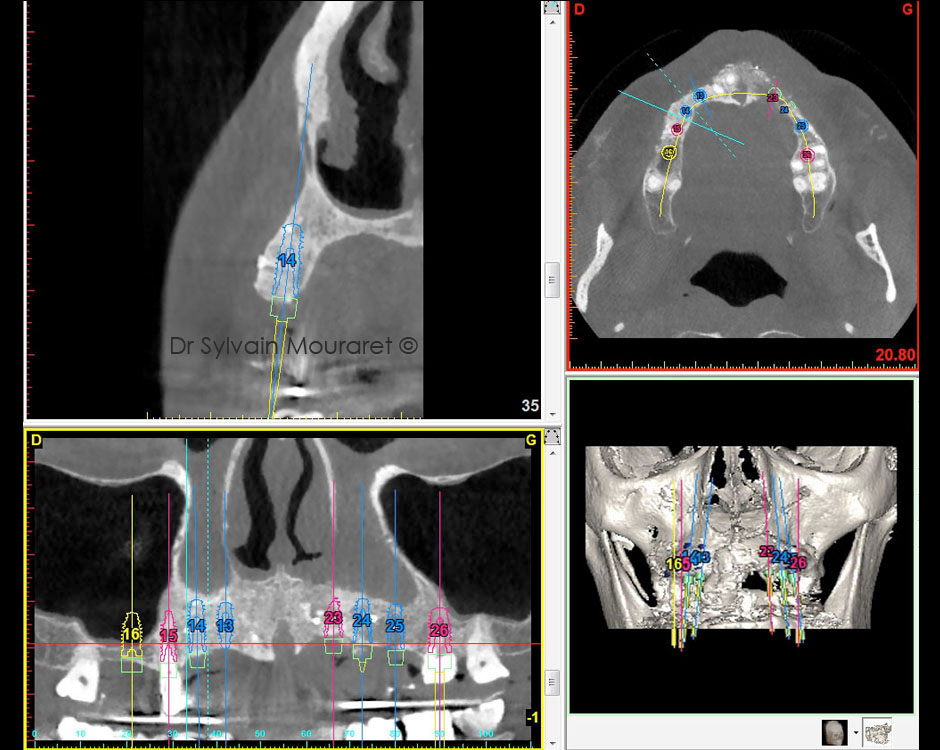

Chirurgie implantaire guidée